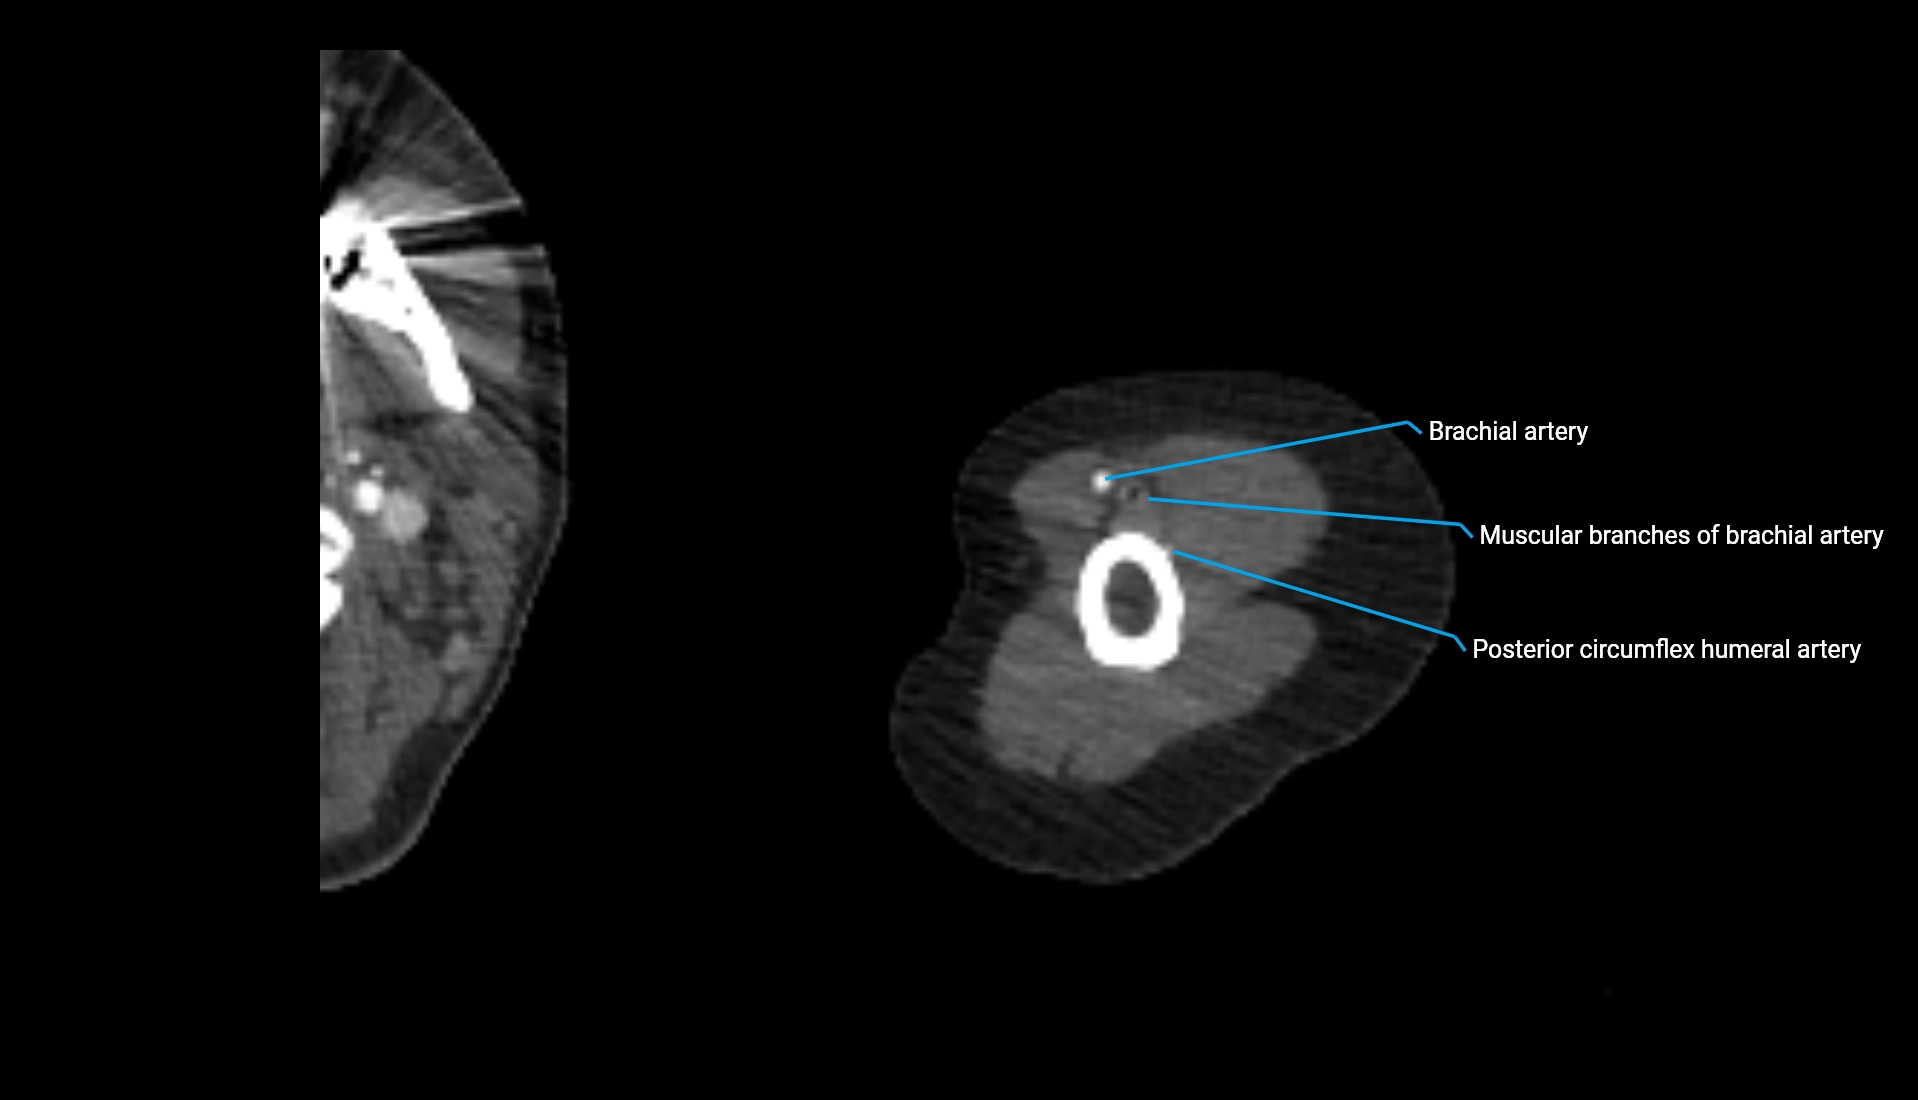

CT Appearance

Non-Contrast CT:

• Cortex: High-density, sharply defined

• Subchondral bone: Dense cancellous matrix

• Articular surface: Smooth concave contour articulating with the capitellum

• Excellent for evaluating bone integrity, alignment, and subtle fractures